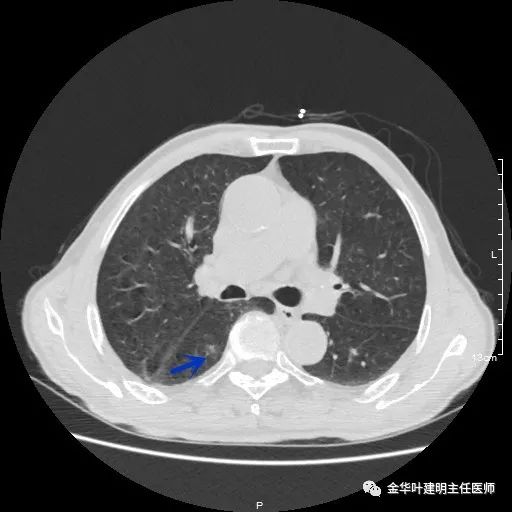

以上示右下叶病灶6。同样是囊腔型病灶,但较前几个范围小,可囊壁同样为磨玻璃影,也是较为典型的囊腔型肺癌表现,单灶来看可下叶背段切除。